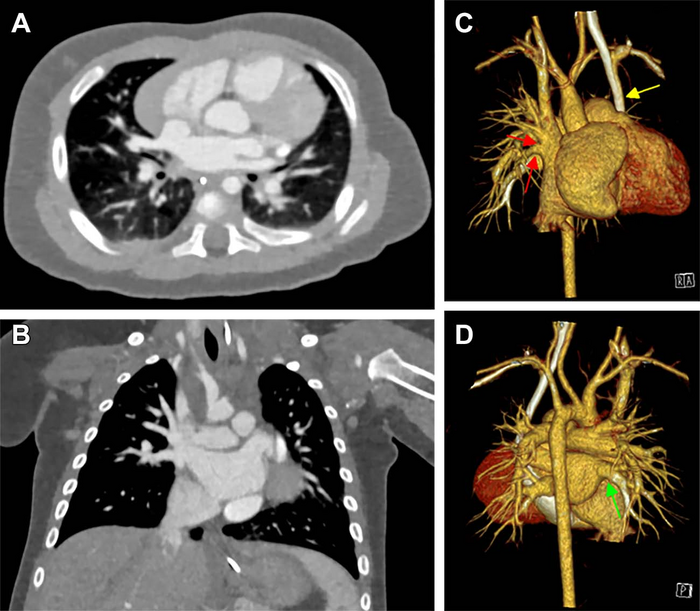

image: Cardiac photon-counting CT (PCCT) in a 174-day-old male infant with complex congenital heart defect. (A) Contrast-enhanced axial PCCT image shows sonographically suspected sinus venosus defect with partial anomalous pulmonary venous connection. (B) Contrast-enhanced coronal PCCT image. (C) Anterior view of three-dimensional reconstruction shows a partial anomalous pulmonary venous connection of two separate lung veins from the right upper and middle lobe to the right superior vena cava (red arrows) and a persisting left superior vena cava (yellow arrow). (D) Three-dimensional reconstruction, posterior view. The diagnosis was confirmed at PCCT, and PCCT allowed for visualization of the partial anomalous pulmonary venous connection of two separate lung veins from the right upper and middle lobe to the right superior vena cava. One lung vein drains correctly to the left atrium (green arrow). A sinus venosus defect, an atrial septum defect, an enlarged right atrium and a persisting left superior vena cava are shown. The only regular confluence of a single right lung vein into the left atrium is shown (D; green arrow). Image quality was rated as 5 of 5 (optimal). view more